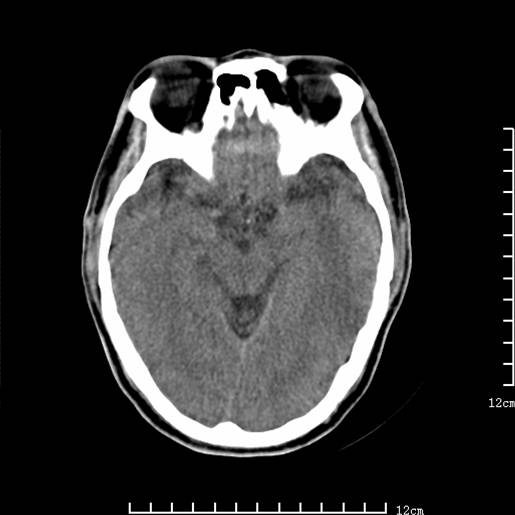

以下图像分别是3月25日凌晨及下午图像、3月27日、4月16日的ct图像。

3月25日凌晨